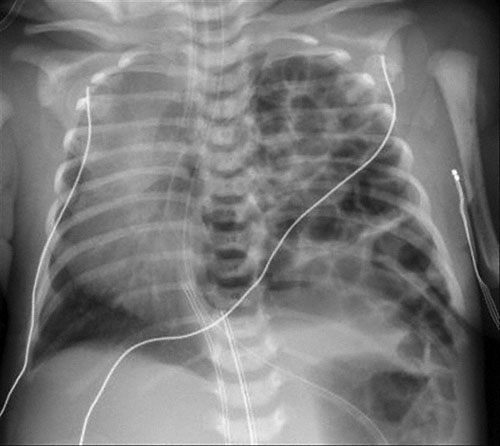

19. Question

A 3200-g (7-lb 1-oz) male newborn is delivered at 38 weeks’ gestation to a 21-year-old primigravid woman. The newborn develops respiratory distress and cyanosis within 5 minutes of delivery. Physical examination shows a barrel-shaped chest and scaphoid abdomen. Cardiopulmonary examination shows absent air entry on the left side, with a shift of heart sounds to the right side of the chest. Arterial blood gas analysis on room air shows hypoxia and acidosis. A chest x-ray is shown. Which of the following is the most likely diagnosis?